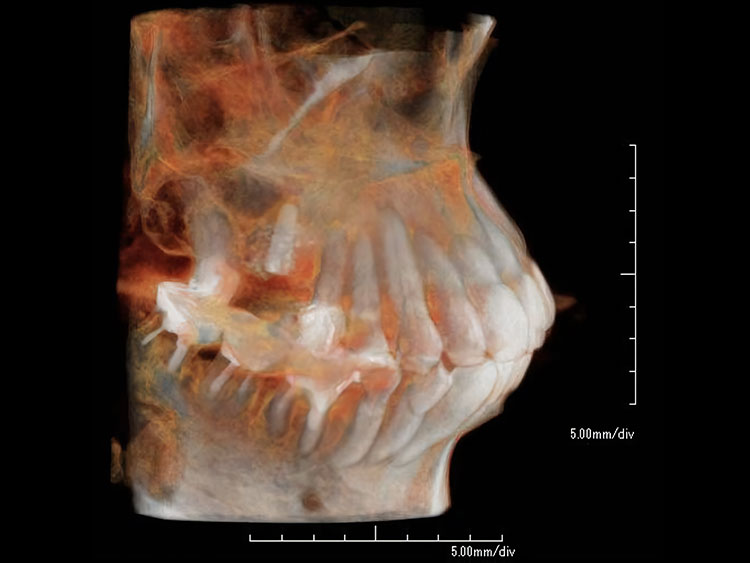

2.インプラントを埋め込む

CT事前にシュミレーション

シュミレーション通りにインプラント埋入

局部麻酔のもと、顎の骨にチタン製のインプラントを挿入します。 このインプラントが 新しい歯の土台となります。